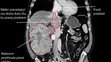

Zaujímavosti zo sveta FOTO: Mal akoby dve hlavy. Mužovi odoperovali vzácny nádor gigantickej veľkosti Ľubomíra Ivanková 5. 3. 2024